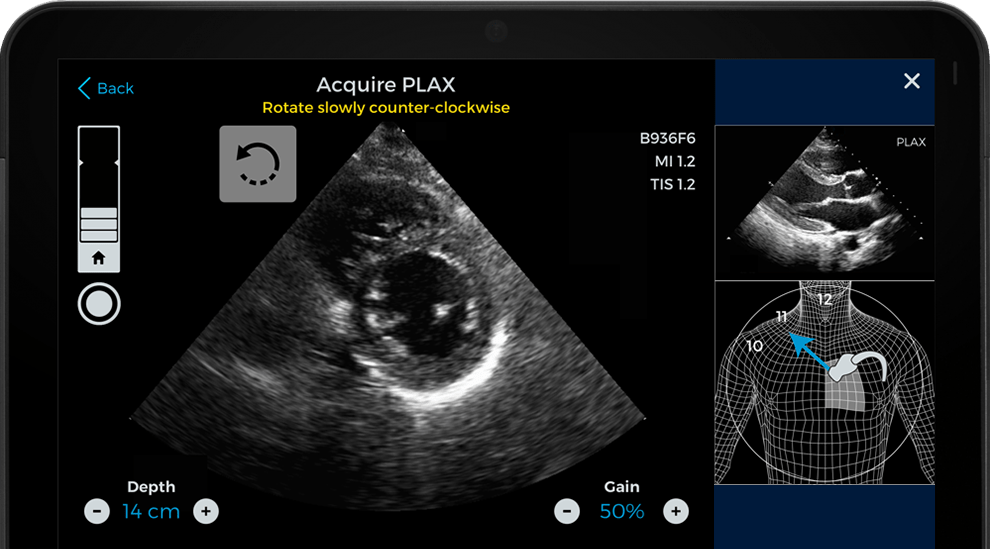

Uyumlu olduğu teşhis amaçlı ultrason sistemlerine eklenti olarak çalışan yazılım yapay zekayı, kullanıcının, kalbin teşhis kalitesine sahip görüntülerini yakalamasına yardımcı olmak için kullanmaktadır. Caption Guidance isimli bu yazılımın, farklı imalatçıların ürettiği tüm ultrason sistemlerinde çalışması hedefleniyor. Bugün ise yalnızca Teratech’in ürettiği ultrason cihazları ile kullanılabiliyor.

De Novo premarket incelemesinin bir parçası olarak Caption Guidance yazılımının incelendiği bir çalışma yapılmıştır. Bu çalışmada, sonografi konusunda az tecrübesi olan sekiz kayıtlı hemşirenin, ekokardiyografi görüntüleri almalarına yardımcı olmak için bu yazılım kullanılmıştır. Yakalanan görüntüleri değerlendiren kardiyolog ekibi, görüntülerin teşhis amaçlı kullanmak için oldukça yüksek kalitede olduklarını farketmişlerdir.

Caption Health bu yazılımın, hiç ultrason deneyimi olmayan birine bile kalbin yüksek kaliteli görüntülerini alma imkanı verdiğini iddia ediyor. Bu, doktorların kliniklerden çok çeşitli şekilde faydalanabilmelerine ve bazılarının böyle bir yazılım olmadan yapamayacakları işlemleri yapmalarına olanak sağlayacaktır. Şirket, Acil Servis odalarının, kritik bakım ünitelerinin ve anesteziyoloji bölümlerinin Caption Guidance’ın en yaygın kullanım alanları olmasını beklemektedir.